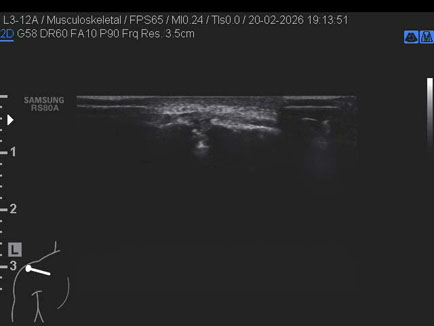

Data inserimento: 24/02/2026

Ecografia del: 20/02/2026

Strumento: Samsung

Sonda: Lineare

Età Paziente: M 20 anni

Commento all'esame: presenza di “os acromiale” (“mesoacromion”): mancata fusione di uno o più centri di ossificazione durante l’adolescenza (circa 5% della popolazione); coesiste lieve iperemia sinoviale acromion-claveare in maschio ventenne.

Conclusioni: presenza di “os acromiale” - mesoacromion (presence of “os acromiale” - mesoacromion).

Realizzazione: Dr. F. Pietro Tarini - Gubbio (PG)